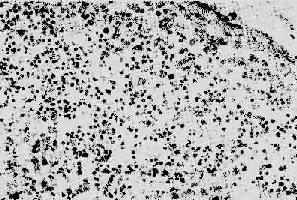

1.淋巴樣組織的變化早期及中期,淋巴結腫大。鏡下,最初有淋巴濾泡明顯增生,生發中心活躍,髓質出現較多漿細胞。隨后濾泡的外套層淋巴細胞減少或消失,小血管增生,并有纖維蛋白樣物質或玻璃樣物質沉積,生發中心被零落分割。副皮質區的淋巴細胞(CD4+細胞)進行性減少,代之以漿細胞浸潤。晚期的淋巴結病變,往往尸檢時才能看到,呈現一片荒蕪,淋巴細胞,包括T、B細胞幾乎均消失殆盡,無淋巴濾泡及副皮質區之分,僅有一些巨噬細胞和漿細胞殘留(圖4-15)。有時特殊染色可顯現大量分枝桿菌、真菌等病原微生物,卻很少見到肉芽腫形成等細胞免疫反應性病變。

圖4-15 AIDS淋巴結

淋巴細胞明顯減少,無淋巴濾泡及副皮質區之分